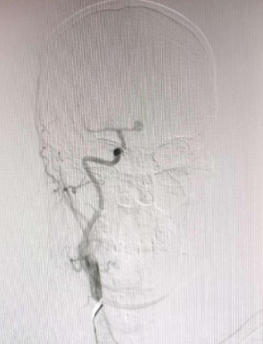

近日,沧州市中心医院神经血管介入二科为一名突发蛛网膜下腔出血的患者实施手术,成功“拆弹”,使患者转危为安。 据了解,患者陈先生(化名),55岁,在某天夜间突然感到剧烈头痛,并伴有恶心和呕吐症状,这些症状持续了整整一天。入院1小时前,他的不适感愈发明显,逐渐陷入昏迷状态,对疼痛刺激已无反应。家属见状,立即将陈先生送往当地医院就诊。医生迅速对陈先生进行了初步检查,结合患者的症状和病史怀疑陈先生可能因动脉瘤破裂导致蛛网膜下腔出血,情况十分危急。于是,当地医生立即联系沧州市中心医院神经血管介入二科团队,家属在了解清楚情况后,果断决定带患者转往沧州市中心医院。 (图一) 患者到达沧州市中心医院后,神经血管介入二科团队立即展开了紧张的救治工作,迅速为陈先生安排了脑血管造影检查。造影结果清晰地显示:陈先生右侧前交通动脉瘤成囊状,相对宽颈,大小约为7.0*6.9*4.2mm,瘤顶指向上方,形态不规则。同时,左侧大脑前动脉显影良好,其余血管未见明显异常(图一)。 (图二) 面对如此紧急和复杂的病情,神经血管介入二科团队凭借丰富的经验和精湛的技术,迅速制定了详细的手术方案——全麻下行颅内动脉瘤介入栓塞术。微导管选择好栓塞部位后,依次送入不同规格的弹簧圈填充动脉瘤。最终造影提示动脉瘤的栓塞情况良好(图二),瘤体周围的血管没有狭窄,双侧大脑前动脉的远端分支显影良好。整个造影过程中,患者的生命体征平稳。在团队的共同努力下,手术顺利进行,医生成功将陈先生体内的“炸弹”——动脉瘤进行了妥善处理。患者回到病房后,予心电监护和吸氧,给予镇静、预防抽搐、缓解血管痉挛、补充血容量和抑酸等治疗。患者恢复期间病情逐渐好转,顺利出院。 什么是颅内动脉瘤? 颅内动脉壁局限性、病理性膨起,普遍存在于全球成年人群中。颅内动脉瘤破裂是导致自发性蛛网膜下腔出血的首位病因,且多发生在55~65岁的人群中。尽管不同地区的死亡率有所下降,但大多数患者仍遗留有明显的神经功能障碍,这给家庭和社会造成了沉重的负担,严重影响了患者的生活质量。因此,颅内动脉瘤是当前严重影响到世界人民生命安全的疾病。随着医学器械技术的发展,动脉瘤栓塞介入术、血流导向装置植入术、动脉瘤夹闭术等技术日趋成熟。 姜红升主任携领神经血管介入二科团队提醒您:颅内动脉瘤是脑中的“定时炸弹”,动脉瘤破裂会导致蛛网膜下腔出血,致残率高、死亡率高。其主要症状为剧烈头痛,如突发难以忍受的头痛症状,不容小觑,应及时到医院进行诊治。未出现动脉瘤破裂的患者,应及时控制高血压、糖尿病、高血脂症、抽烟、酗酒等高风险因素,并及早根据个人动脉瘤特征选择合适的治疗方式。 神经血管介入二科 国家临床重点专科创建单位,河北省临床重点建设专科,沧州市临床重点专科,目前拥有医护人员20人、医生6人,护士14人,其中医学博士1人,硕士研究生导师1人,副主任医师2人,主治医师1人,住院医师3人;主管护师3人,主持科研项目3项,荣获河北省卫健委二等奖1项;近三年内发表SCI论文数篇,其中一篇发表于中科院分区1区杂志。主要诊疗范围:脑血管病的外科手术与介入治疗。我科与北京天坛医院、宣武医院、天津医科大学总医院、天津市环湖医院、河北省医科大学第二医院、山东大学齐鲁医院等长期保持密切的的友好合作关系,在颅内动脉瘤、颈动脉狭窄等疾病诊疗方面,神经血管介入二科基于疾病特点以及患者具体情况不同,个体化的为患者制订适合的手术方案;我们科室的发展理念:以患者的医疗安全为重中之重、严格把控医疗质量、业务水平精益求精、通过热情诚恳的服务理念,不忘初心、以德立科,在患者朋友们和医院内外树立良好的口碑。 科室诊疗范围: 1.蛛网膜下腔出血、颅内动脉瘤开颅夹闭术、颅内动脉瘤介入栓塞术、血流导向装置植入术、瘤内扰流装置植入术等; 2. 脑血管畸形、硬脑膜动静脉瘘的外科手术切除与介入栓塞术; 3. 颅内外血管狭窄、烟雾病等导致的脑梗死、短暂性脑缺血发作等,颈动脉、椎动脉、锁骨下动脉支架及颅内动脉支架植入术、颈动脉内膜剥脱术、颅内外血管搭桥术; 4. 急性脑梗塞动脉溶栓、取栓术; 5. 静脉窦血栓形成溶栓、取栓术,良性颅内压增高综合征,静脉窦支架置入术、岩下窦采血辅助诊断垂体瘤等; 6. 慢性颈动脉闭塞再通术、脑血管畸形介入栓塞+外科手术切除等、颅内高血运肿瘤术前供血动脉栓塞等复合手术; 7. 脊髓血管造影,硬脊膜动静脉瘘栓塞术; 8. 神经危重症的救治。 门诊地址:沧州市中心医院脑科院区北2楼1诊室 病区地址:沧州市中心医院脑科院区北6楼 科室电话:0317-2179505 姜红升 神经血管介入二科副主任(主持工作),党支部书记,医学博士,硕士研究生导师,副主任医师,毕业于天津医科大学神经外科专业,先后于北京天坛医院、复旦大学华山医院、天津医科大学总医院、山东大学齐鲁医院等学习进修,主要擅长脑血管疾病的外科手术及介入治疗。主持科研项目多项,荣获河北省卫健委二等奖一项。 专业擅长:脑动脉瘤、血管狭窄、动静脉畸形、烟雾病等脑血管病的手术及介入治疗。